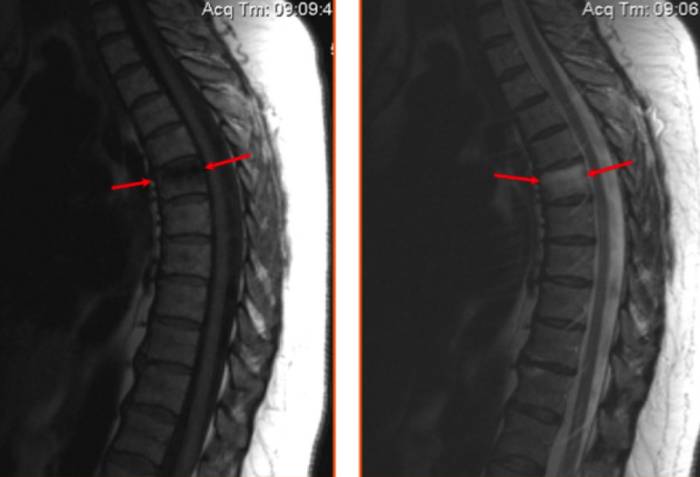

На МР-томограмме представлен остеохондроз шейного отдела позвоночника с формированием задней грыжи диска между пятым и шестым шейными позвонками, сдавливающий позвоночную артерию: стрелкой указан сформировавшийся в итоге участок инфаркта (нарушения процесса кровообращения) спинного мозга